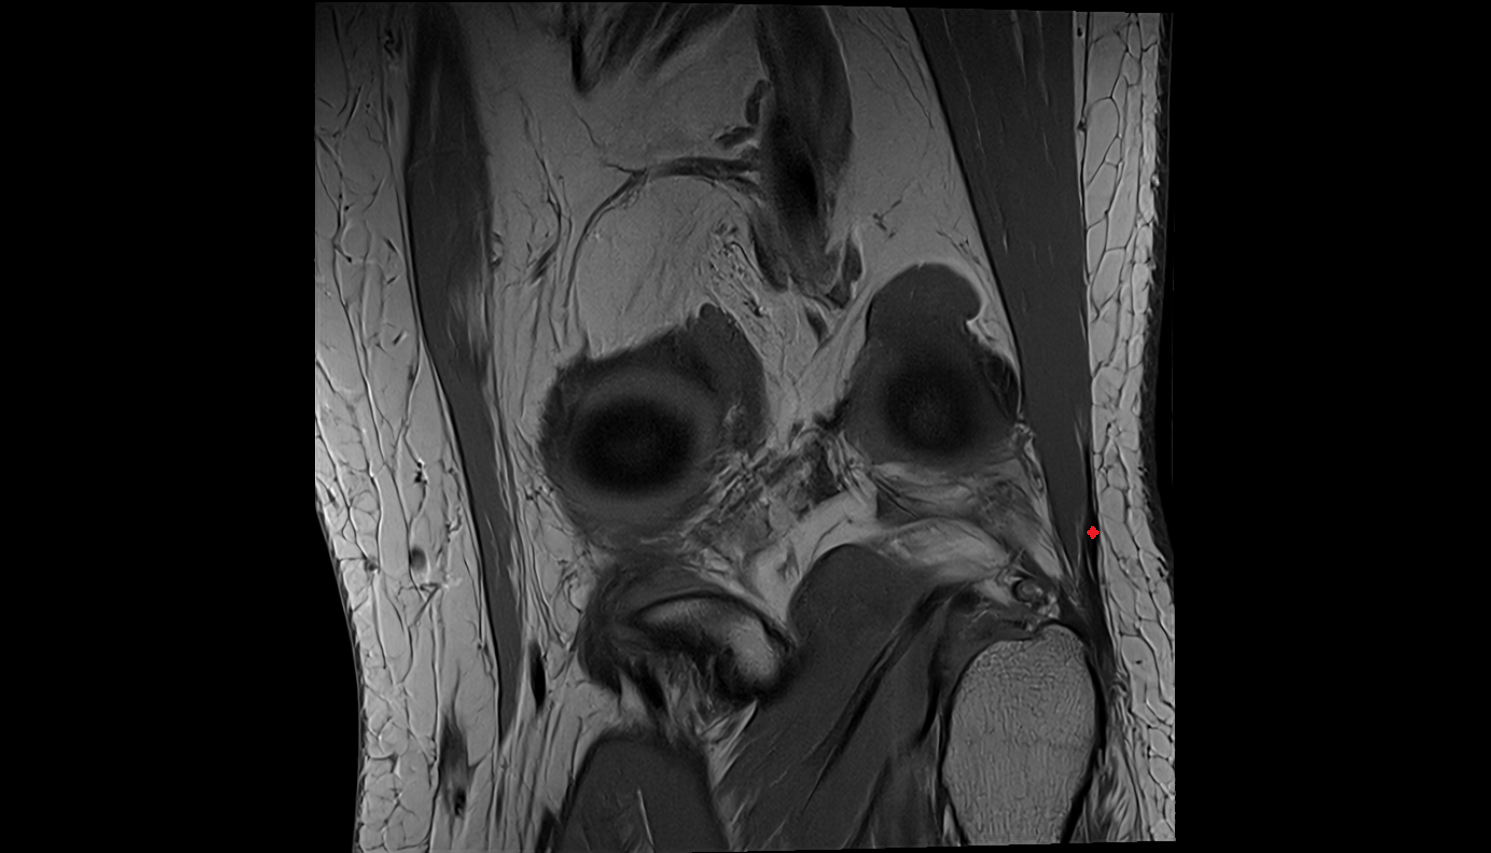

- Knee Joint